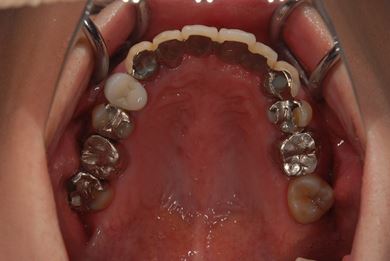

| カテゴリー | 【インプラント治療】【セラミック治療】 | ||||||||||||||||||||||||||||||||

| 性別/年齢 | 女性 / 40歳 | ||||||||||||||||||||||||||||||||

| 治療方針 | 右下奥、骨再生法によりインプラント治療を可能にする。 | ||||||||||||||||||||||||||||||||

| 治療内容 | インプラント3本(GBR、テンポラリーインプラント+仮歯)、ハイブリッドセラミックブリッジ3本、ハイブリッドセラミッククラウン2本 | ||||||||||||||||||||||||||||||||

| 総治療費 | 1,524,338円 | ||||||||||||||||||||||||||||||||

| 治療期間 | 1年0ヶ月 |